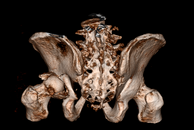

Zur weiterführenden Diagnostik einer Beckenverletzung steht uns modernste radiologische Bildgebung mit 3D-Rekonstruktion zur Verfügung. Auch intraoperativ ist eine 3D-Bildgebung bei laufender Operation möglich. Zur Therapie von vorderen und hinteren Beckenring-Frakturen favorisieren wir Platten-Osteosynthesen offener Reposition, aber auch minimal-invasive Therapieoptionen und transkutane Verschraubungen.

Frakturen der Hüftgelenkspfanne

Frakturen der Hüftgelenkspfanne (Azetabulumfrakturen) sind häufig komplizierte Frakturen. Die Schwierigkeit der Versorgung liegt in der exakten Wiederherstellung der konkaven Gelenkfläche. Auch bei optimaler Versorgung kann sich aus einer Azetabulumfraktur ein frühzeitiger Hüftgelenksverschleiß entwickeln.